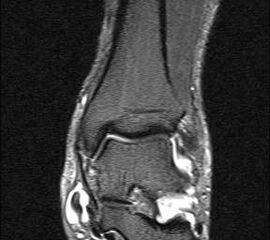

Aufgrund der geringen Zuverlässigkeit der klinischen Untersuchung und der konventionell radiologischen Bildgebung ist die Bildgebung der Wahl die Kernspintomographie (Szeimies 2014). Allerdings bestehen auch bei der Kernspintomographie klare Grenzen, vor allem hinsichtlich der Beurteilung der mechanischen Stabilität. Zuverlässige Aussagen sind möglich zum Ausmaß der Verletzung, insbesondere welche Bandanteile betroffen sind, sowie zu Begleitverletzungen. Chun et al. 11 berichteten über eine Sensitivität von 84% und eine Spezifität von 93,5% für Läsionen des Deltabandes im MRT. Befunde im MRT umfassen eine flächige Ödematisierung und Einblutung entlang des Deltabandes, meist unter Aussparung der kräftigen Pars tibiotalare posterior. Ein gewellter Verlauf, sowie eine Unterbrechung der Kontinuität der Faszikel sind Zeichen eines strukturellen Schadens. Teilweise finden sich Knochenkontussionsödeme, aber auch kortikale Absprengungen am lateralen Talusrand, der Talusschulter und am Außenknöchel. Fast immer findet sich ein Gelenkerguss (Abbildung 4).